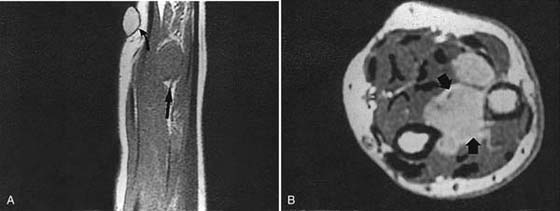

MRI is of great value in defining soft tissue abnormalities (Figs. 13-17 to 13-19, all online). In the evaluation of tumors, it cannot provide a specific diagnosis, but it can define the size of the lesion and the extent of involvement of marrow and neurovascular structures (Fig. 13-20, online).27 Other soft tissue abnormalities diagnosed more easily by MRI include ganglions, ligament tears, and cartilage abnormalities (Fig. 13-21).28,29 Dorsal wrist pain can be attributed to hypertrophy of the dorsal capsule as well as ganglions that may be occult and not palpable. Patients with dorsal wrist pain of unknown origin are therefore candidates for MRI evaluation. MRI is especially helpful in diagnosing tears of the scapholunate and lunotriquetral ligaments, particularly when dissociation of the scapholunate is not evident on plain films.30 Excellent depiction of the TFC can be achieved with MRI, but the image must be interpreted carefully; thinning of the disk occurs in many patients, but a tear of this structure is not diagnosed unless an avulsion from the ulnar or radial insertion can be observed.31-33

images

Figure 13-17 Synovial sarcoma. A, Sagittal magnetic resonance image showing a soft tissue mass (arrow). The white object (curved arrow) is a marker (raw almond) placed over the palpable mass (straight arrow). B, Axial magnetic resonance image obtained after contrast enhancement demonstrates the mass again (arrows) and shows that the neurovascular bundle is encased by tumor.